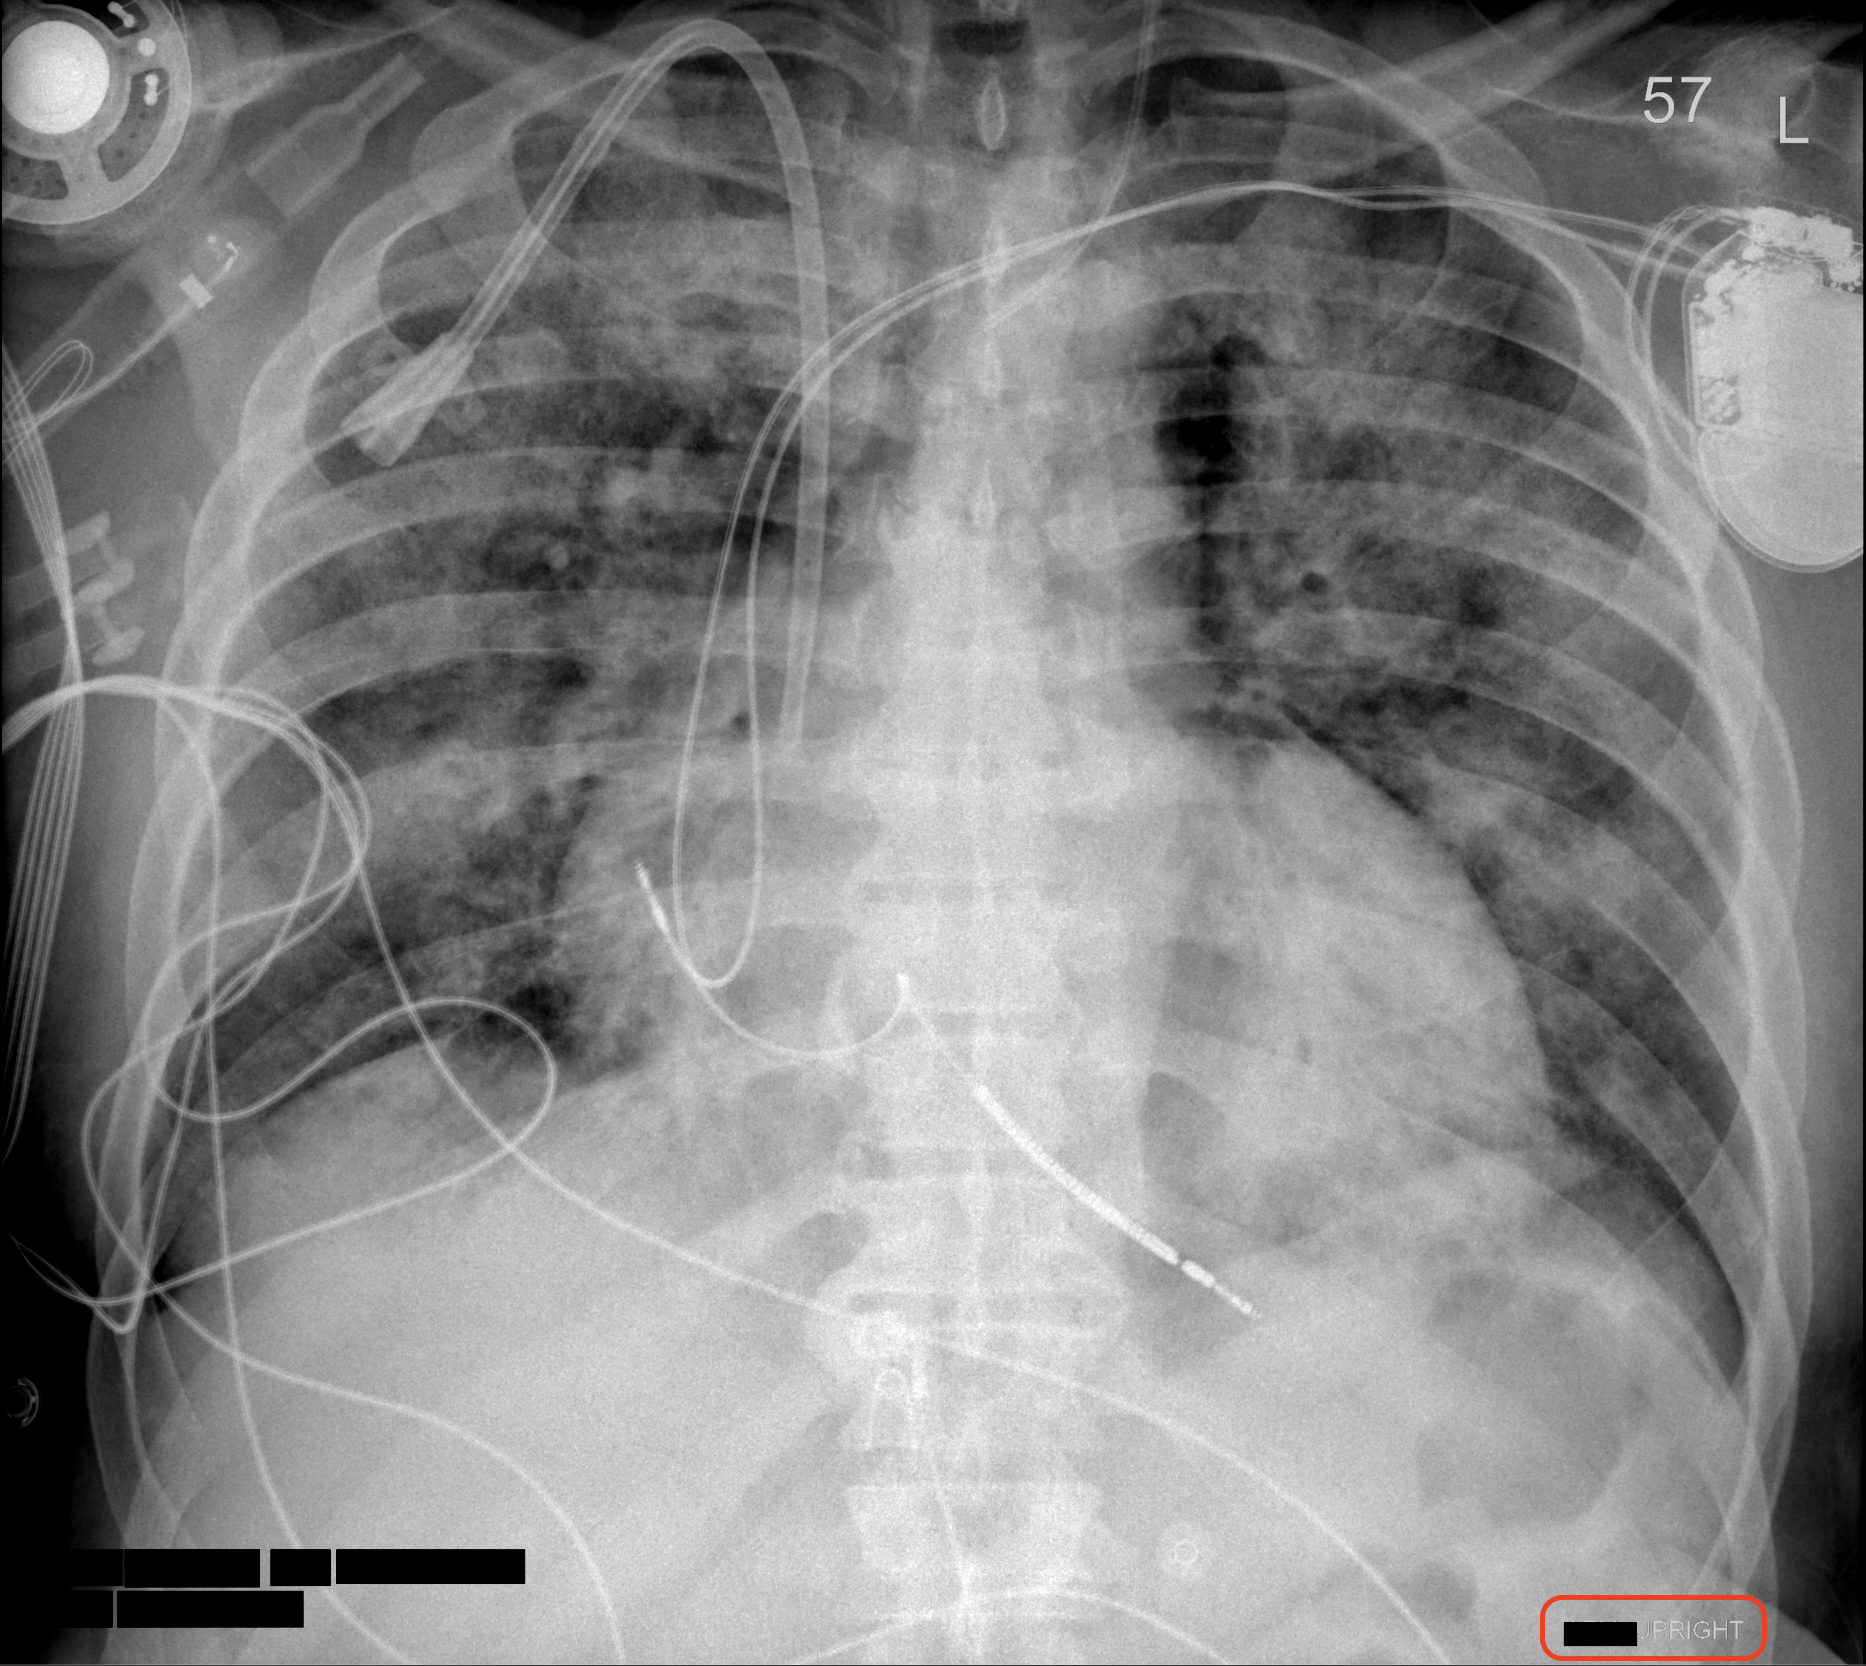

The Digital Imaging and Communications in Medicine (DICOM) standard, which is widely adopted for medical imaging, embeds patient-related information as metadata in the DICOM files. For some modalities, manufacturers embed certain PHI/PII, such as patient name and date of birth, in the pixel matrix of images, such as for ultrasound (Bidgood Jr et al., 1997; Mildenberger et al., 2002). DICOM data elements used as attributes of information objects are identified by numeric tags (group number and element number), with even-numbered group numbers representing standard attributes, and odd-numbered groups representing private attributes specific to manufacturers. In a DICOM medical image, many identifiers are stored as predefined attributes in the DICOM header. These include the Patient’s Name (0010, 0010), and Patient’s Birth Date (0010, 0030), etc. PHI/PII can be present in either such structured DICOM attributes intended for the purpose, but also in free-text fields, such as Additional Patient History (0010, 21B0). Header and pixel data of DICOM images must, therefore, be de-identified. Fiugre 1 shows a DICOM image comparison before and after deID. The well-defined structure of fixed DICOM attributes allows for semi-automatic deID to remove corresponding PHI/PII with relative reliability, but requiring verification, using tools such as The Radiological Society of North America (RSNA) Clinical Trial Processor (CTP) (Freymann et al., 2012), DICOM Library (Macdonald et al., 2024), and XNAT platform (Clunie et al., 2024). Recently, the technologies of medical image deID have evolved from strict rule-based systems to include hybrid approaches such as deep-learning-based systems for object character recognition in pixel images, and large language models (LLMs) for detection of PHI/PII within free text fields (Langlois et al., 2024; Kopchick et al., 2022). The DICOM deID process for removing sensitive information needs to follow instructions of a set of deID standards such as those in DICOM PS3.15 (National Electrical Manufacturers Association (2025), NEMA) for PHI/PII fields to remove or modify, and satisfy HIPAA DeID requirements.

4.2 Pixel deID

Optical character recognition (OCR) techniques and tools were widely used by MIDI-B participants to de-identify the burned-in PHI/PII from the pixel images. In the action of <pixels_hidden>, four teams performed well. The errors occurred due to false positives or false negatives in the deID process of burned-in text. However, it is difficult to conclude the performances because only a very small number of pixel images with burned-in PHI/PII were present in the MIDI dataset and evaluated. For the <pixels_retained> action, half of the submissions failed to perform correctly. While nearly all teams achieve accuracy in the total score, there are still many errors in pixel image deID, including false positives (FP), and false negatives (FN). Figure 3 demonstrates several instances of improper pixel image deID. The top-left image shows the original image. The top-right image depicts the post-deID image, which includes false negatives (the PHI/PII information remains in the top red box) and false positives (some white blocks appear in the bottom red box). The bottom-left image shows a different post-deID of the same image with false negatives, where the date of birth still appears in the red box. Finally, the bottom-right image demonstrates over-removal because of the false positives, where the anatomical structure image has been altered beyond the removal of PHI/PII information.